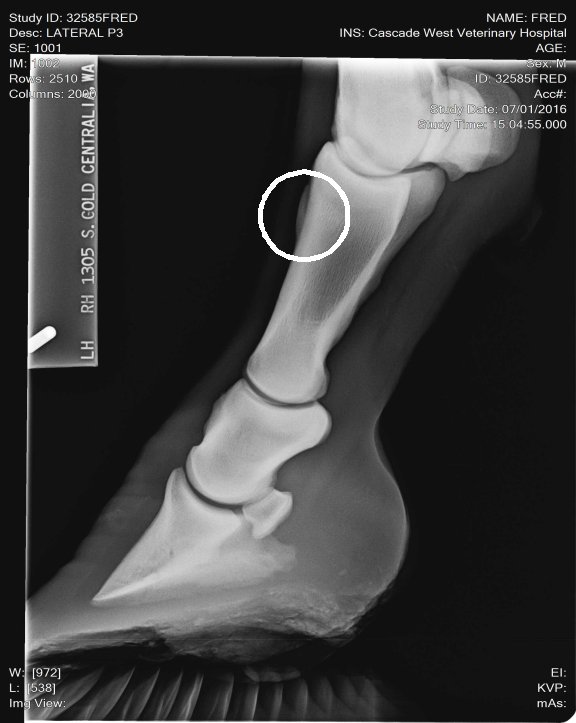

Location: Washington | Here is the correct spot circled!

(unnamed (1)c.jpg)

Location: Lost in the swamps | My opinion these X rays don't look bad. I don't see any involvement in the joint spaces. I've seen a lot worse. He's got really long toes, you need to show your farrier these x rays and have him shorten and round his toes to quicken his break over is very important for horses dealing with ringbone. long toes create a lot of torque! This can also lead to lamine inflammation. The p-1 and p-2 is a low motion joint so it can actually fuse and the horse still have soundness. Your p2 and coffin joint is where you don't want any issues of ring bone. And I don't see any there. The upper pattern has some oddity near the seasmoid bone. Just curious did your vet mention anything? |